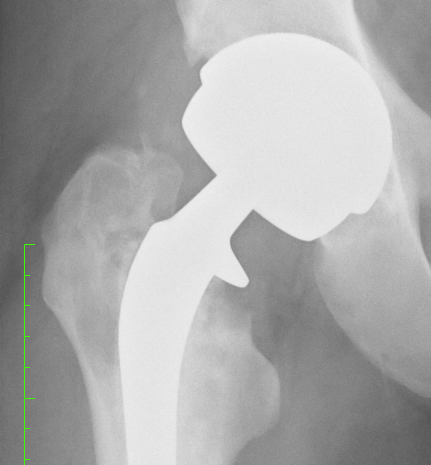

Both hips were examined and pain confirmed on both – and restricted painful movement. It also appeared that the right leg, with the hip replacement was longer than the left leg.

The x-rays confirmed the arthritis in the left hip and this is going to need replacing.

However, it was the right hip, with the Smith & Nephew Birmingham Spectron total hip replacement which caused the most interest:

- Severe oestolysis around the hip – tissue damage.

- Bone erosion (gone totally) for several centimeters below the collar on the inside leg side.

- Damage to the bone on the outside leg side – mottled and insubstantial-looking.

- Signs of movement of the femoral stem of the hip implant – lines down either side and possible bone damage – the cement contains ceramic and this can then act as a grinding past as the stem moves. This has the potential to release more metal ions.

- These signs of movement may explain the feeling of “popping in and out” that I feel – but without dislocation of the hip prosthesis.

We reviewed my X-rays and confirmed the osteolysis and bone loss. The health of the bone at the top of the femur is a concern and I am going to have a nuclear medicine bone scan tomorrow morning to see what is going on with the blood flow to and around the bone.

The movement of the prosthesis, or lines suggesting movement within the femur where obvious (it seems?).

Had some new X-rays done today – two months since the last ones – seems to me that there is more osteolysis and bone loss – possibly some fragments but I am not a medical doc and I haven’t discussed these with the surgeon yet. Will do on the day of the surgery.

What is interesting is 3 radio-opaque spots showing up in the pelvic area – not sure what those are.

Quality of the photo’s below – OK for an iPhone 4 shot of the X-Rays held up by my son against a white background!